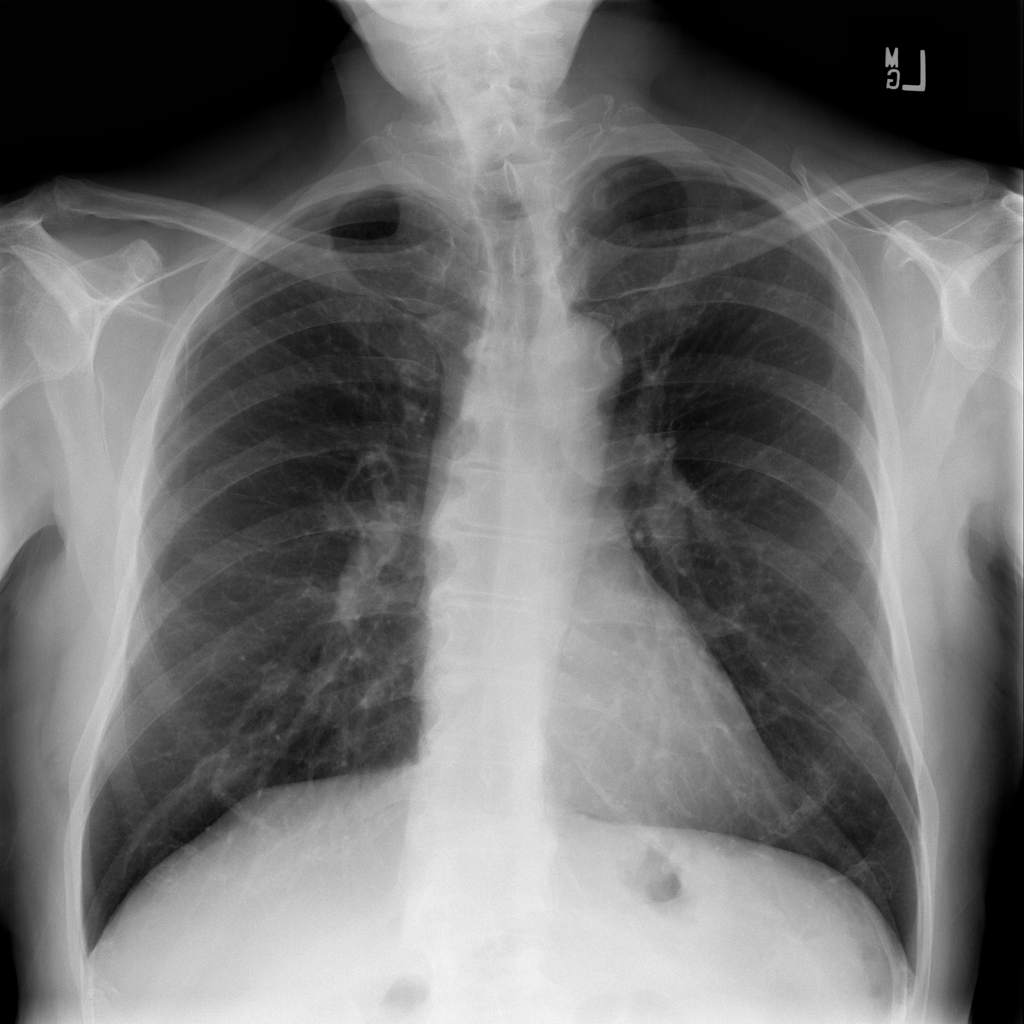

Nodule

A nodule is a small rounded opacity in the lung or chest field. It is a descriptive imaging finding that can be benign or more concerning depending on size, appearance, and context.

Showing up to 90 reference images for Nodule.

PAT-FB8F · IMG-000Nodule

PAT-FB8F · IMG-000

PA